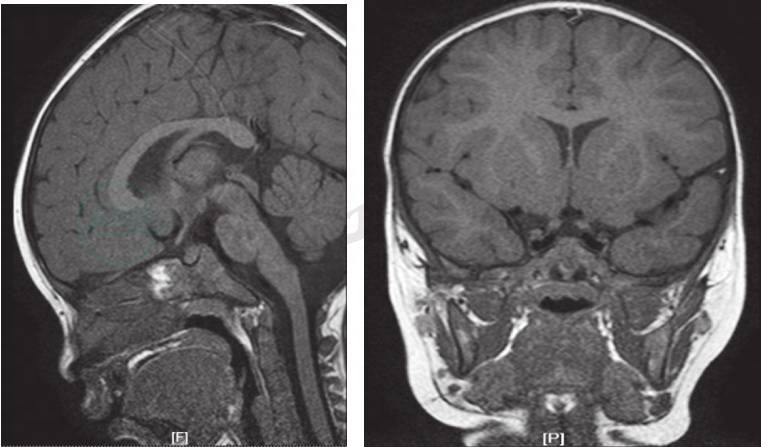

辅助检查:垂体增强MRI:脑垂体体积正常。增强检查垂体可见一弱强化灶(大小约2mm×3mm)(图1)。胸片:双肺间质性改变。

图1 门诊完善的垂体增强MRI

肺朗格汉斯细胞组织细胞增生症,诊断依据:①慢性咳嗽、干咳为主,夜间咳嗽明显,活动后气促;肺部HRCT,表现为双肺多发高密度斑片影,小叶间隔增厚,双肺散在大小不等囊性透光区;②反复出现皮疹,分布在躯干部及头皮部,表现为大小不一、形状不规则红色斑丘疹,伴有少许渗出;③中枢性尿崩症,表现为多饮多尿,尿比重降低,脑垂体受累,脑垂体增强MRI显示垂体可见一弱强化灶(大小约2mm×3mm);④骨髓像显示朗格汉斯细胞。